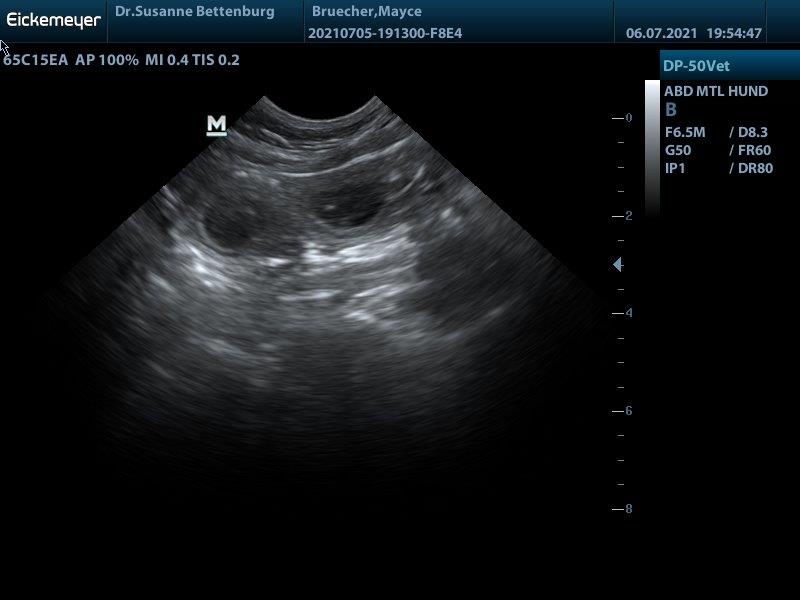

Hurra Mayce ist tragend!!! sodass die Welpen mitte August geboren werden

F-Wurf Mayce wurde am 14.06.2021 von Theo gedeckt. In dem Wurf erwarte ich braune und schwarze Welpen